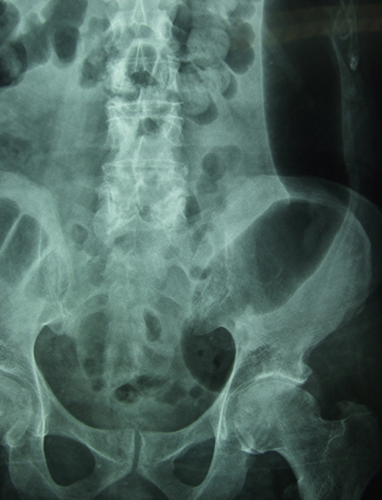

osteosíntesis fractura fémur